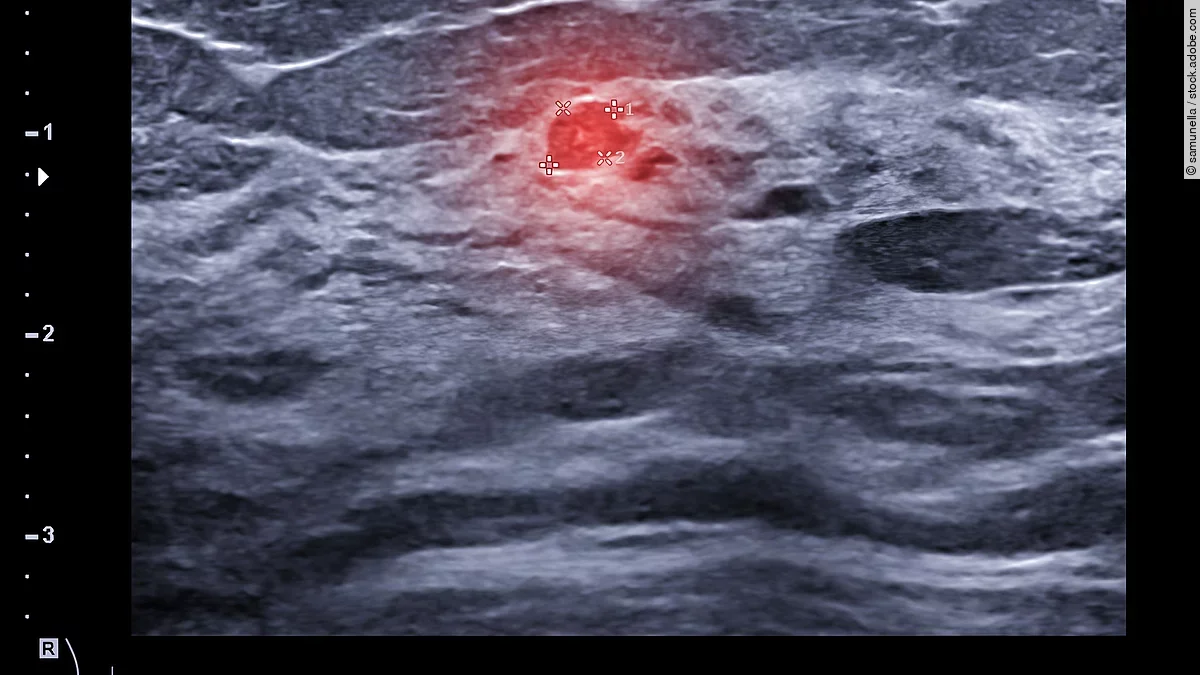

Vor allem in der Mammasonographie kann sich KI als wichtiges und nützliches Tool erweisen. So gibt es neben dem handgeführten Ultraschall auch automatisierte Brustultraschall-Scanner, die 3D-Ultraschalldatensätze generieren. Diese könnten mittels KI analysiert werden. Studien belegen bereits die hohe Genauigkeit der KI-Befundung.

Der KI-gestützte 3D-Ultraschall kann auch in der Brustkrebsdiagnostik als Ergänzung zur Mammographie zum Einsatz kommen. Diese gilt weiterhin als beste Methode zur Früherkennung, stößt aber bei dichtem Brustgewebe an ihre Grenzen. Die Sensitivität dieser Untersuchung sinkt dann von fast 90 auf 50 Prozent. Genau an dieser Stelle kommt die KI zum Einsatz. „Diese Lücke könnte der KI-gestützte automatisierte Brustultraschall, eingesetzt im Rahmen eines Screening-Settings, schließen, denn der Ultraschall erkennt auch in dichtem Drüsengewebe zuverlässig Karzinome“, so Farrokh. Laut einer Studie könnten in 1 000 Untersuchungen dadurch drei zusätzliche Karzinome entdeckt werden.